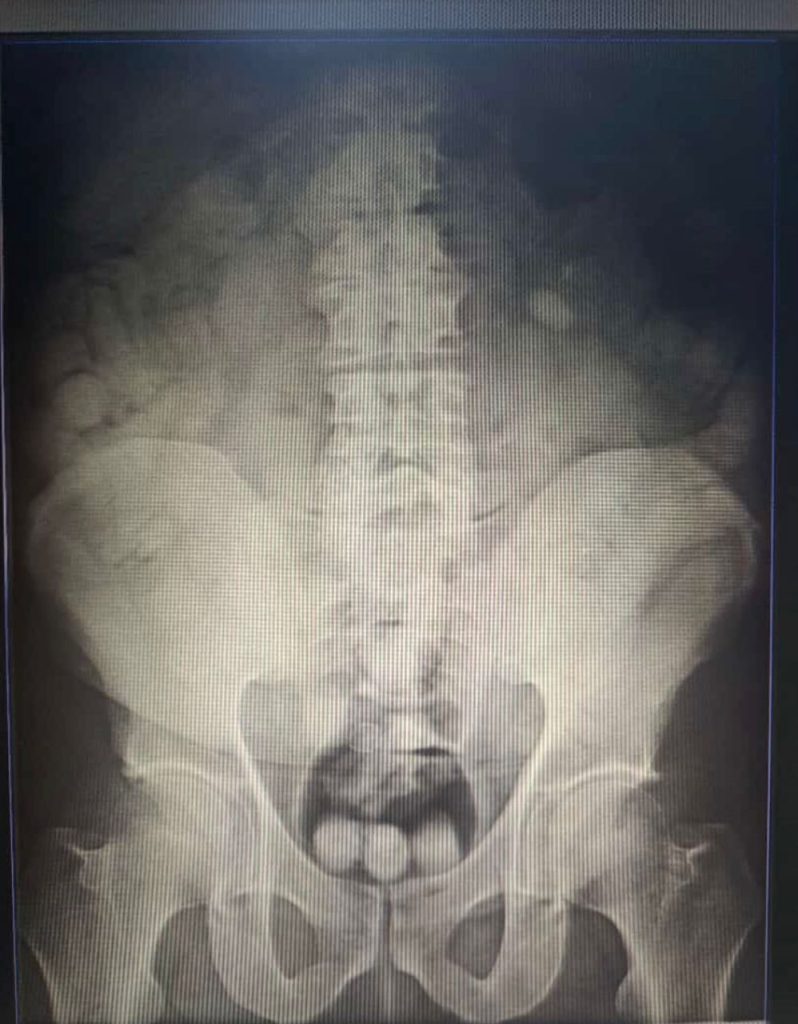

Al ser interrogado, manifestó que llevaba en 80 dediles de presenta cocaína en su estómago. De inmediato, fue detenido y trasladado al hospital de Agua Blanca donde le hicieron rayos X e inició el proceso de expulsión, hasta ahora solo llevan 31, a la espera de los otros.